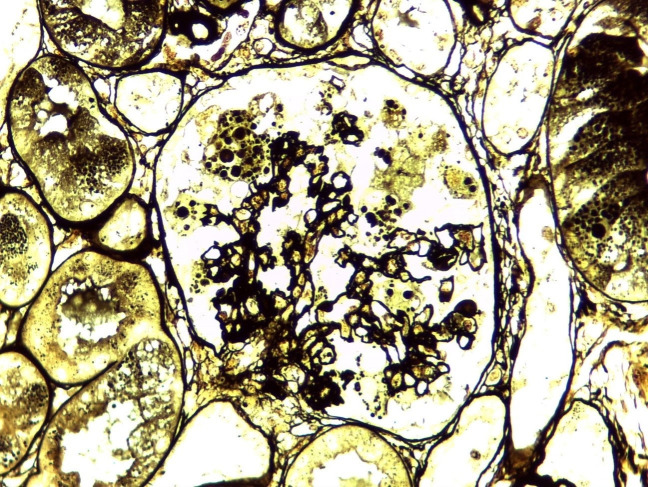

Collapsing glomerulopathy (CG) has a severe course typically associated with viral infections, especially HIV and parvovirus B19, systemic lupus erythematosus (SLE), among other etiologies. A 35-year-old woman with recent use of a JAK inhibitor due to rheumatoid arthritis presented with a 2-week history of fever, cervical adenopathy, and facial erythema. After admission, anemia, hypoalbuminemia, proteinuria, and severe acute kidney injury were noted. SLE was diagnosed and parvovirus B19 DNA was detected in serum samples. Kidney biopsy showed CG without any typical features of lupus nephritis. The patient was treated with prednisone and presented marked improvement of anemia and kidney function after a few weeks. In this case, the patient with SLE presented CG possibly caused by parvovirus B19 infection associated with homozygous apolipoprotein 1 (APOL1) G1 genotype, which has been described as a determinant risk factor for this glomerulopathy. It is not clear whether SLE had a causal relationship with glomerular disease or was a concurrent cause. Treatment can be challenging in such a context, as no antiviral drug is efficient and immunosuppression has no discernable benefit, although steroid use was efficient in treating renal manifestations in this case.